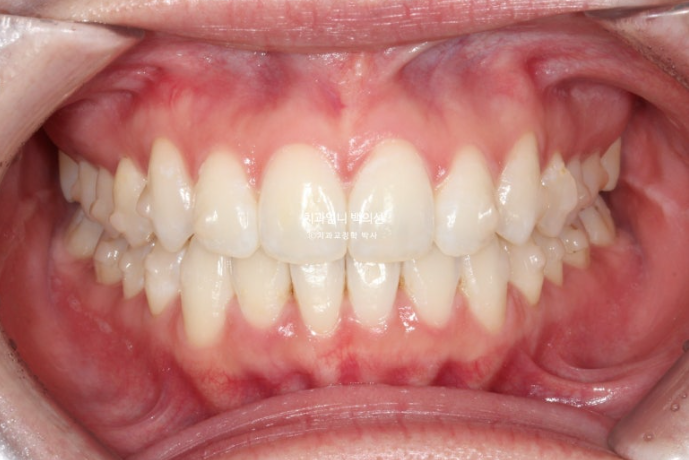

첫 세트 14개 장치를 모두 낀 후 모습입니다

중심선은 잘 맞고

원래 좋았던 어금니 교합은 잘 유지 되었고

배열도 좋습니다.

인비절라인라이트 재제작 기회가 1번 있지만 경과가 좋아 재제작 없이 마무리 했습니다.

총 치료기간은 5개월 입니다.